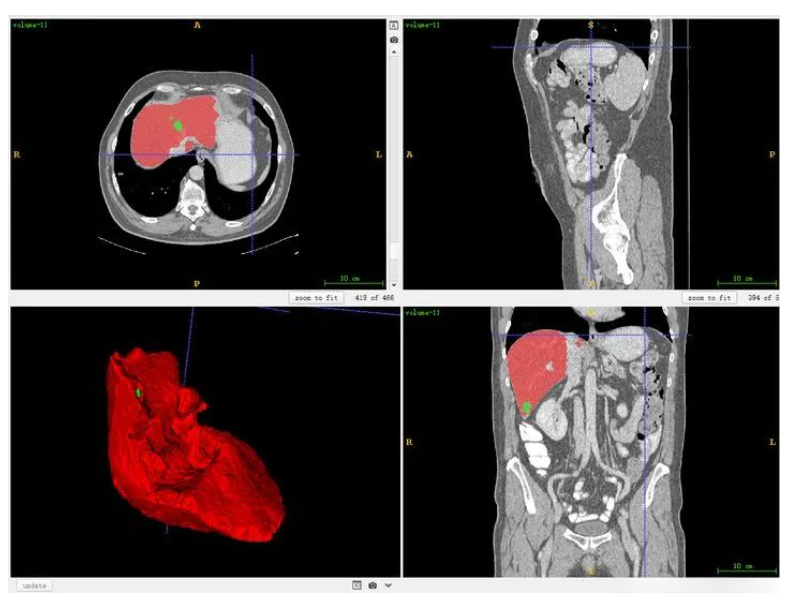

首先要明确一下和人体对应的方向,其中三个窗口对应三个切面,对应关系如下图所示,按照字母索引即可。例如,左上图对应R-A-L-P这个面,是从脚底往头部方向看的切面(即z方向),另外两张类似。

红色切面为矢状面,紫色切面为冠状面,绿色切面为横断面

也可以同时将分割结果导入,对比观察。

对于标注不太严谨的地方也可以精细化修改。当然公开集的话,绝大多数都挺好的。自己标注也是类似。(如果显示不太清晰,对比度太低,需要在软件中调节窗宽和窗位)